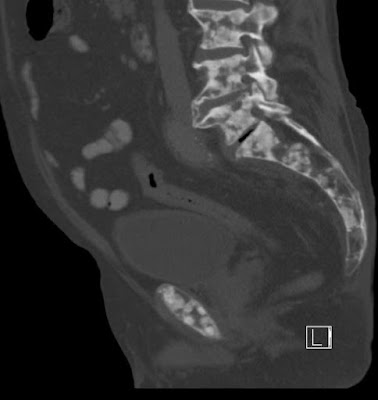

- Kidney stones